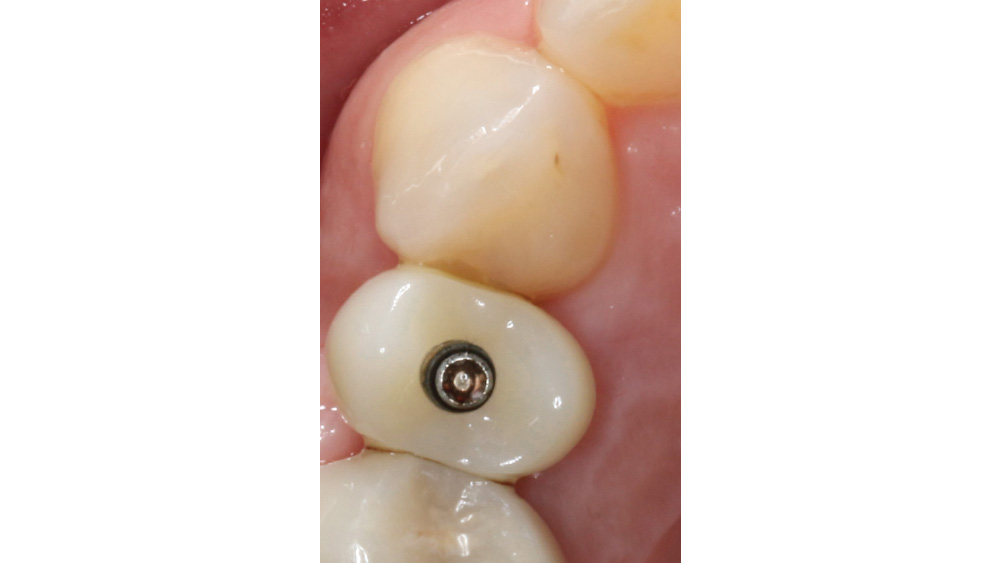

CASE REPORT

The following case, which I performed alongside Dr. Stephanie Tilley of Pensacola, Florida, illustrates the use of both surgical techniques for the same patient, who presented with edentulous spaces in the areas of both right and left maxillary first bicuspids. Due to varying soft-tissue volume on each side of the arch, implant surgery was performed using a flapless procedure for one site, while the attached gingiva was reflected to expose the available hard tissue for the other. As a result of proper site evaluation, treatment planning and restorative-driven implant placement, both surgical techniques led to successful outcomes for the patient.